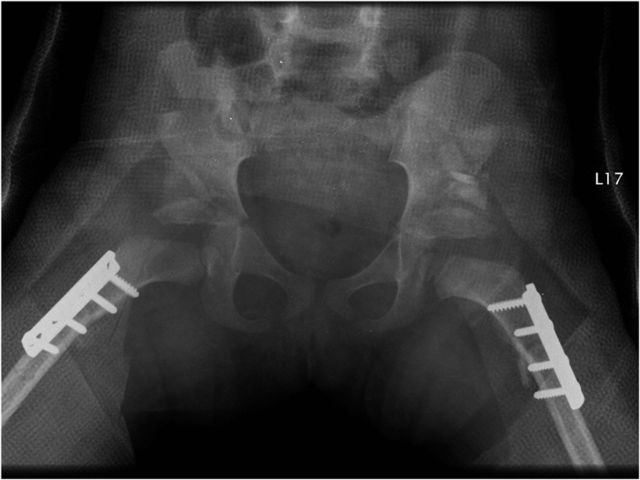

The patient shown in Figures 26 through 29 and Video 5 was a three-year and six-month-old girl with bilateral developmental dysplasia of the hip that was discovered late (Figs. 26 and 27). The three-dimensional computed tomography (CT) scan in 360° of rotation showed a high posterior dislocation (Video 5). The postoperative radiograph revealed good femoral head reduction in a stable position (Fig. 28). The patient subsequently had the same procedure on the left side under a subsequent anesthesia (Fig. 29).

Fig. 26.

Figs. 26 through 29 Illustrative case (also see Video 5). Fig. 26 Standing anteroposterior radiograph of the pelvis of a three-year and six-month-old girl with bilateral high dislocation of the hip.

Fig. 27.

Bilateral frog-leg lateral pelvic radiograph demonstrating the same high bilateral dislocation with acetabular dysplasia.

Fig. 29.

Postoperative anteroposterior pelvic radiograph made with the patient wearing a cast after the same procedure on the other side.